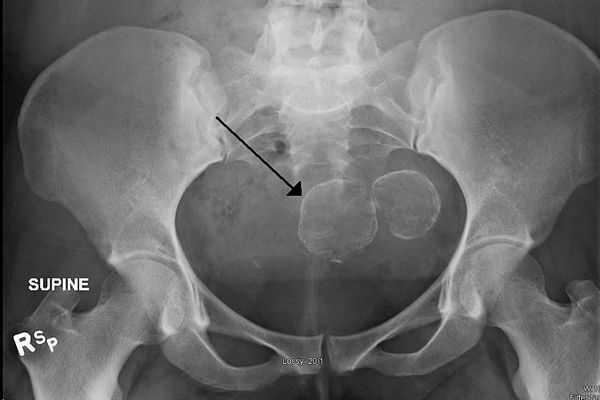

Гистеросальпингография

Гистеросальпингография — ценный метод для диагностики субмукозной фибромы матки. При процедуре полость матки заполняется контрастным веществом, что позволяет хорошо разглядеть на снимках выпирающие в полость матки узлы фибромы.